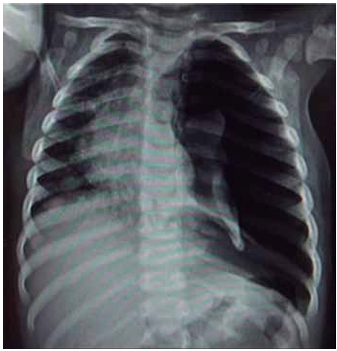

Lactente de 1 ano com diagnóstico de bronquiolite com sinais evidentes de desconforto respiratório. Apesar das medidas de suporte, ausência de melhora clínica e necessidade de intubação (IOT); logo após o procedimento, apresentou melhora da saturação de oxigênio e do padrão respiratório e foi acoplado à ventilação mecânica com parâmetros elevados. Aproximadamente 1 hora depois, iniciou com piora progressiva da saturação (queda sustentada até 78%), diminuição da ausculta pulmonar e da expansibilidade à esquerda, com respiração assincrônica. Averiguada posição da cânula, adequada e não obstruída. Exame físico com aparente piora hemodinâmica, FC = 174 bpm, PA = 64 x 32 (40) mmHg e pulsos finos. Realizada radiografia de tórax a seguir.

(Arquivo pessoal; imagem usada com autorização)

Considerando os dados apresentados, assinale a alternativa que descreve a melhor conduta para a condição atual do paciente.